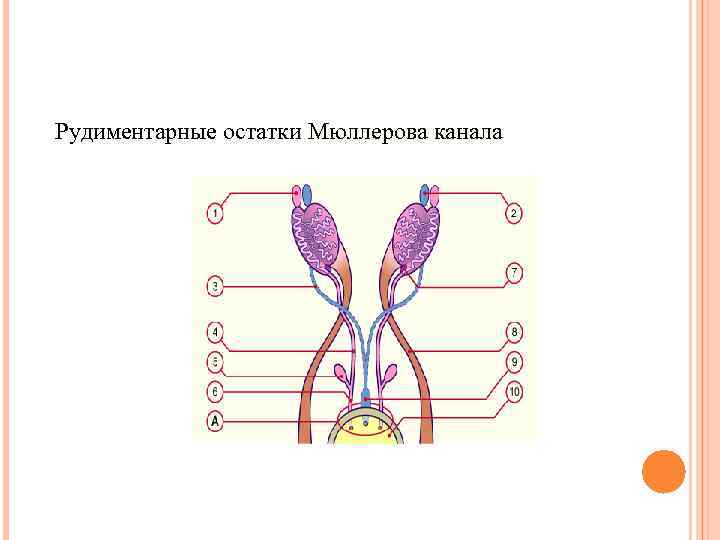

Рудиментарные остатки Мюллерова канала

Рудиментарные остатки Мюллерова канала